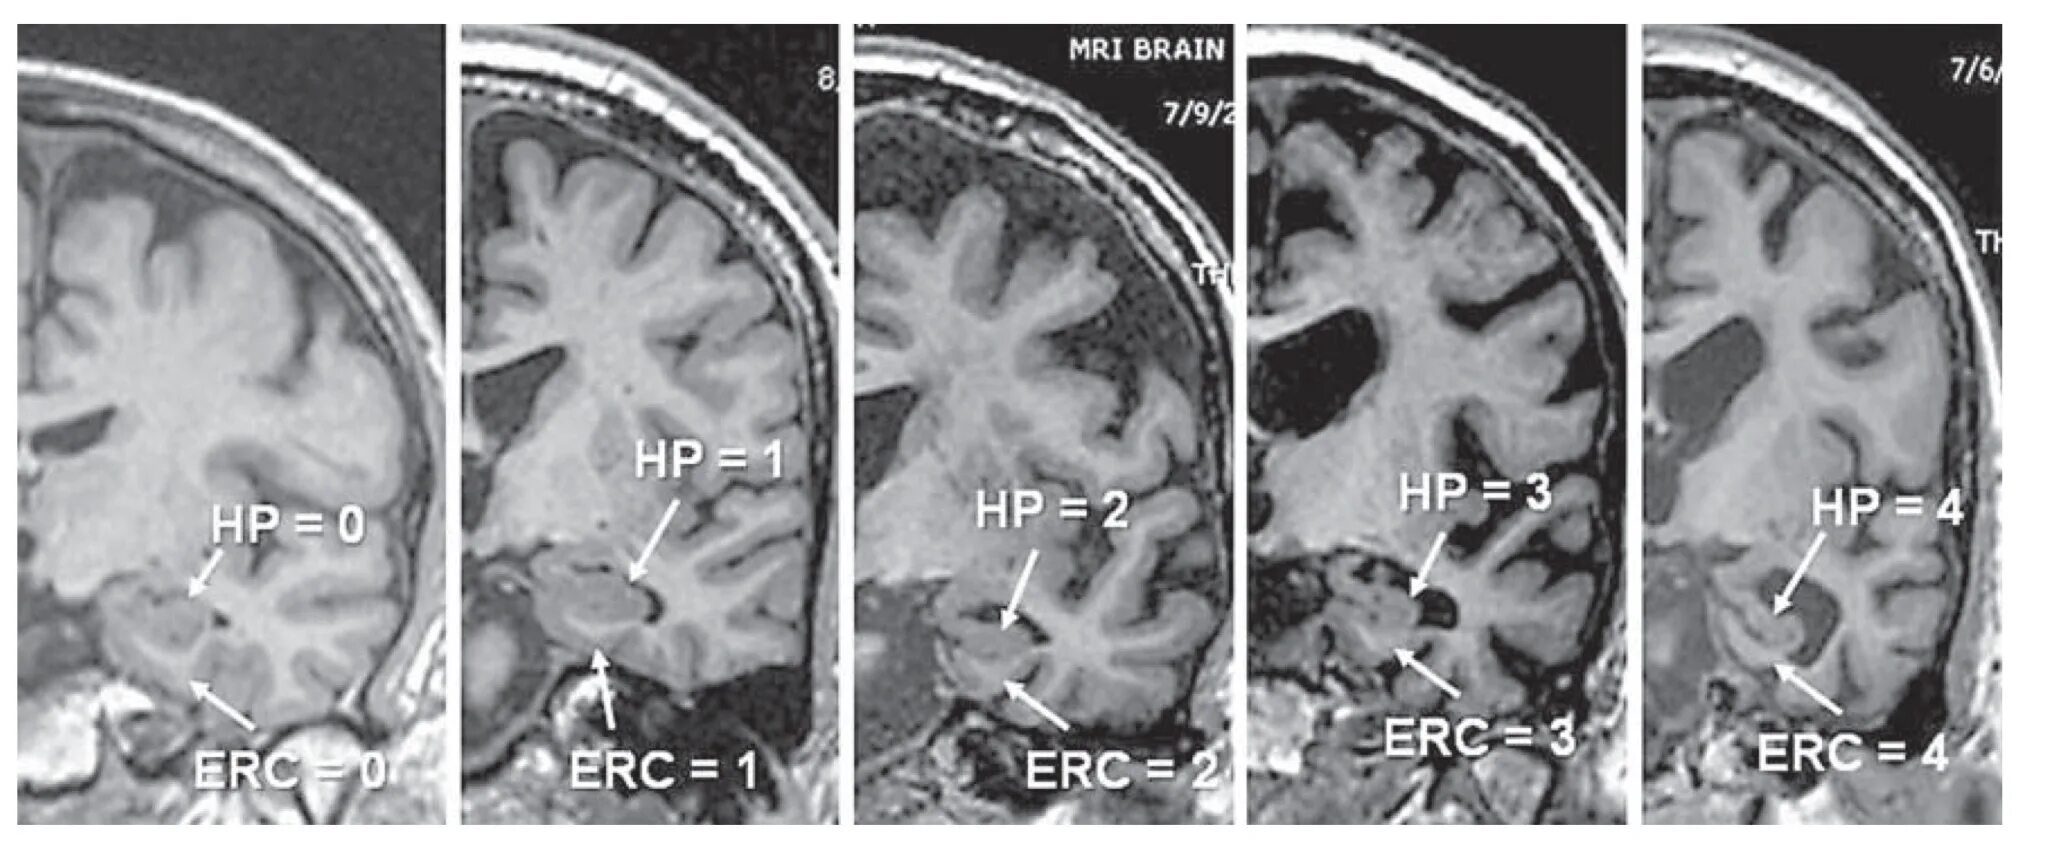

Диффузной биполушарной кортикальной атрофии